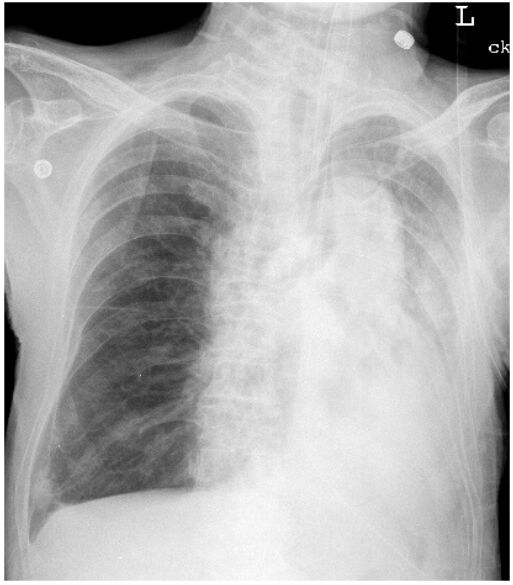

25.慢性阻塞性肺病病人在拔管後,因血氧下降,經緊急插管後胸部X光如下,下列何者最為可能? (A)左肺塌陷(collapse) (B)左側大量肋膜積液 (C)左側呼吸器相關性肺炎 (D)右側氣胸